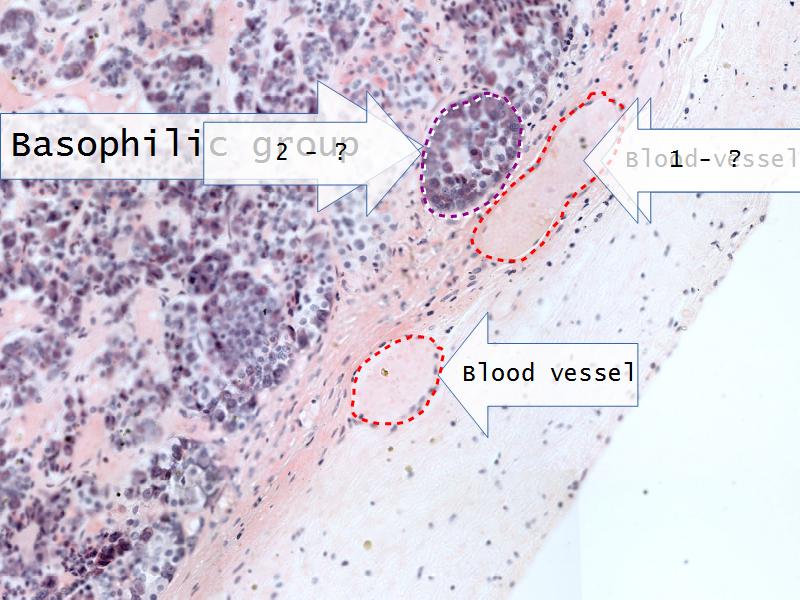

Adrenal glands

Capsule

Cortex - how many zones?

Medulla

Hormones of each?